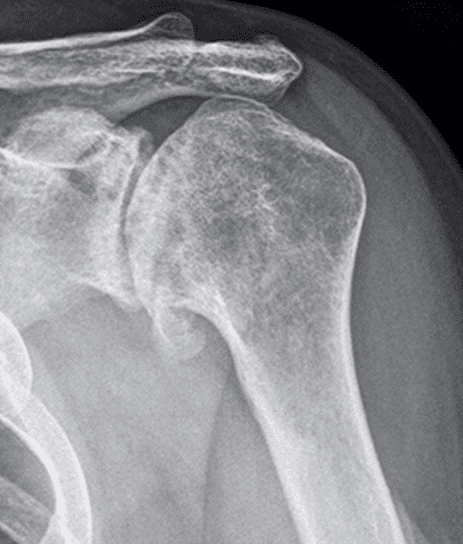

Patient Cases